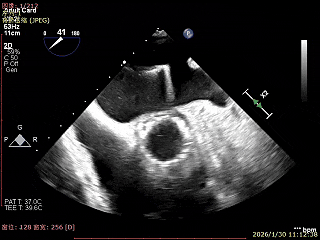

经胸短轴测得瓣口面积约6.1cm2

3区前叶长度约22mm,后叶长度约11.6mm

2区前叶长度约32.2mm,后叶长度约16mm

2区Flail Gap约4mm